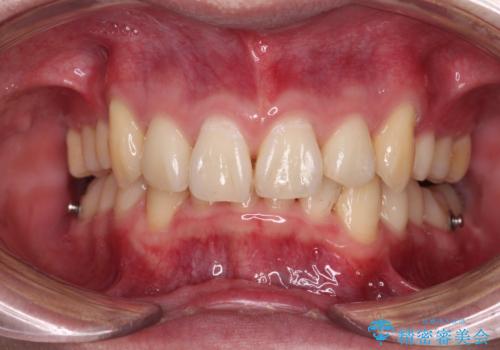

- 八重歯を気にして来院された患者様です。

顕著な上顎の八重歯とディープバイトであったため、上顎の左右第一小臼歯を抜歯することとしました。

犬歯歯根の位置や奥歯の咬み合わせから、ワイヤー装置での治療を強くおすすめいたしましたが、ご本人の強い希望により、妥協的な仕上がりとなることを了解いただき、インビザラインにて矯正治療を行うこととしました。

インビザライン単体で、左右ともに移動の難しい位置に歯根のある犬歯を整えるのは困難と判断し、補助装置を併用することとしました。

ディープバイトや奥歯の咬み合わせなど、インビザライン矯正では限界がありワイヤー装置での治療に及ばない仕上がりとなりました。

ただし、患者様としては八重歯や、それに伴う唇の閉じにくさが改善されたとのことで、納得いく状態での治療終了となりました。